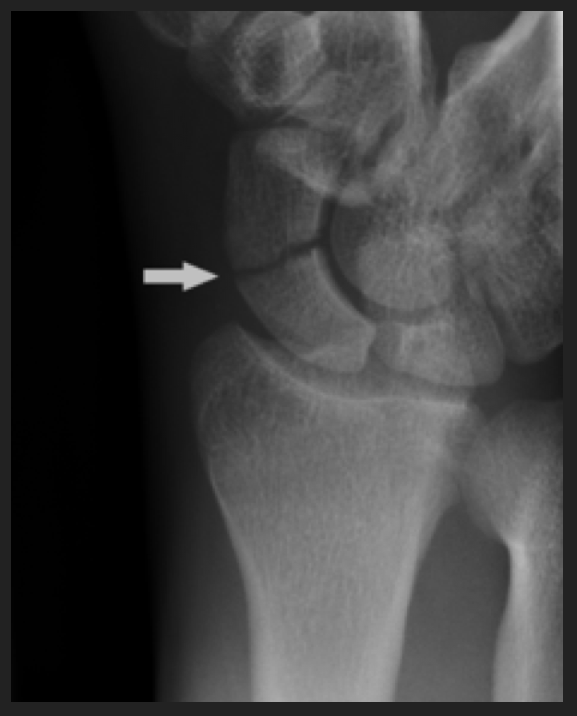

Scaphoide fracture Publié 20 février 2013 à 577 × 716 dans Je vous crois ← Précédent J’aime chargement… Poster un commentaire ou un rétrolien.